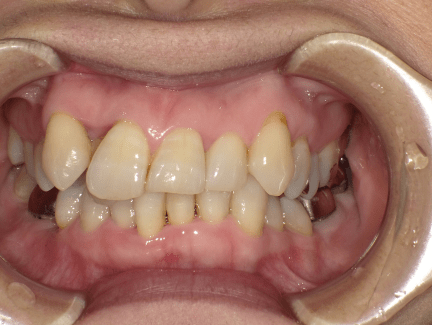

叢生(デコボコ)

原因:歯の大きさと顎の骨の横幅のアンバランス

叢生(そうせい)の原因とは?

一般的には、一つ一つの歯の大きさと顎の骨の大きさとのバランスが悪いことが叢生の原因とされております。

この他にも、子供の歯並びから永久歯への生え変わりがうまくいかなかったり、虫歯などで子供の歯を早くに失ってしまったことで、叢生が生じてしまう方もいらっしゃいます。歯並び・かみ合わせは人生を通して常に変化するものですから、食いしばりの癖が強い方などは年齢を重ねるにつれ叢生がひどくなってきたとおっしゃられる方もおられます。